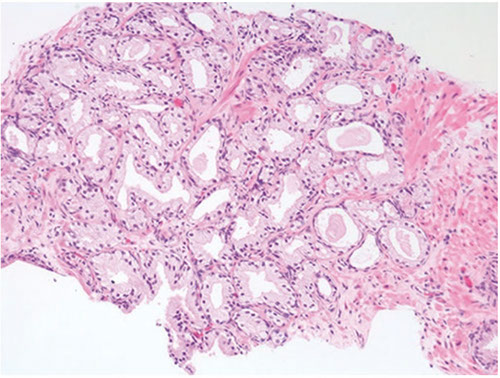

Intraductal Carcinoma of the Prostate (IDC-P)

Intraductal spread of a malignant prostatic AC

- frequently assoc c aggressive and high Gleason score invasive acinar adenocarcinoma

- is a prolif of pleomorphoic malignant cells (with nuclear sizes up to 6x nuclear sizes in adjacent invasive adenocarcinoma)

- expands ductal structures, but has at least a partial / patchy basal cell layer (rules out invasive acinar or ductal AC)

- rarely can be id'd on bx material in absence of infiltrating carcinoma

- vs HG-PIN, has a more dense cribriform pattern with overtly more solid than luminal areas (ie ratio of solid to luminal areas >70%)

- may show small cell-like change

- IDC-P on prostate bx is freq assoc c HG ca and poor px at radical prostatectomy

- thus most likely represents an advanced stage of tumor progression c intraductal spread of tumor in most cases

Infiltrating cribriform acinar AC (Gleason 4 or 5 c comedonecrosis) closely mimics cribriform IDC-P

- most cases if IDC-P would be dx'd as cribriform ca if IHC demonstrating basal cells had not been performed

- in some cases, contour and branching pattern of normal duct architecture suggests the dx of IDC-P as opposed to infiltrating ca

- the tx of IDC-P and infiltrating HG-prostate AC are the same, so distinction not critical on bx

- purely IDC-P at radical prostatectomy is 100% cured by surgery, the same may not be true of an infiltrating ca

- if there is no definitive infiltrating ca on H&E sections and a suggestion of IDC-P in a core, then basal stains are recommended to differentiate IDC-P from infiltrating carcinoma

Ductal AC and IDC-P have significant morphologic overlap

- distinguishing features in ductal AC include tall pseudostratified columnar epithelium c amphophilic cytoplasm, classically aranged in cribriform patterns c slitlike spaces and true papillary fronds

- in contrast, IDC-P has cuboidal cells, cribriform patterns c rounded lumina and micropapillary tufts w/o fibrovascular cores

- basal cells are generally absent in ductal AC, although occasionally there may be partial retention of basal cells as ductal AC can also spread within prostatic ducts